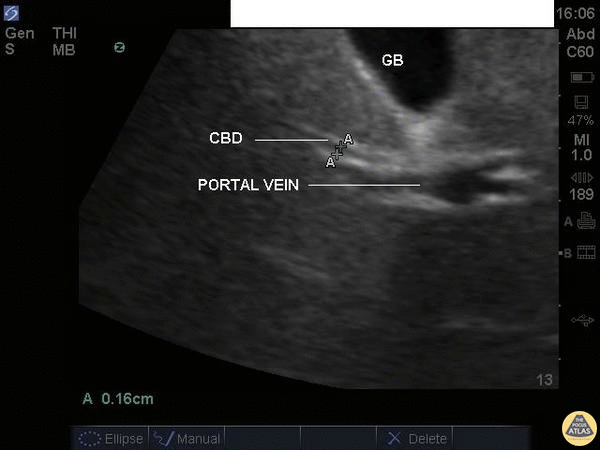

Biliary - Common Bile Duct (Normal Labeled)

A normal common bile duct should be <4mm plus 1mm per decade after 40 years of age. It should be measured from inner wall to inner wall. You should attempt to find the portal triad: the CBD, the portal vein, and the hepatic artery. You may need color flow to find all three. Here the CBD and portal vein are labeled (no labeled hepatic artery). To get better images, especially if you're dealing with a lot of rib shadow, it can be helpful to have your patient take a deep breath and/or roll onto their left side. Justin Bowra MBBS, FACEM, CCPU Emergency Physician, RNSH et al.